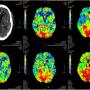

Defying All Odds: Successful Thrombolysis in a Nonagenarian with Posterior Circulation Infarct

Temporal Ependymoma: A Case Study Emphasising Diagnostic Dilemmas and Therapeutic Challenges